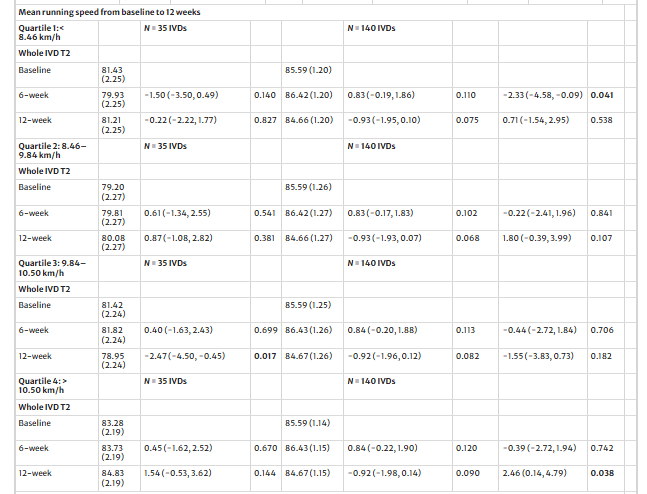

- Факторы вмешательства: Кумулятивный объем бега, средняя скорость бега и доминирующая поверхность для бега (трава, гравий, тротуар или тропа) оценивались с помощью бесплатного приложения Runkeeper. Совокупный объем бега и средняя скорость бега были распределены по квартилям IVD для анализа от исходного уровня до 12 недель. Все модераторы вмешательства сравнивались с контрольной выборкой.

Средняя скорость бега от 10,5 до 11,7 км/ч положительно повлияла на межгрупповой показатель IVD T2 через 12 недель. В то время как средняя скорость бега от 4,4 до 8,5 км/ч отрицательно влияла на IVD T2 только через шесть недель. Бег по траве положительно повлиял на межгрупповой показатель IVD T2 через 12 недель.

Вмешательство в виде бега с ходьбой было разработано как консервативное, что привело к широкому разбросу средних скоростей бега (от 4,4 до 11,7 км/ч) и суммарных объемов бега (от 1,8 до 109,8 км). Хотя это дало возможность провести анализ по подгруппам, он отражает высокую вариабельность фактической "дозы" бега.

Скорость бега и поверхность имеют значение: Наилучшие результаты были достигнуты при скорости бега 10,5-11,7 км/ч. Бег по травяной поверхности также оказывал положительный эффект на IVD. Индекс массы тела не оказал никакого модераторского влияния.